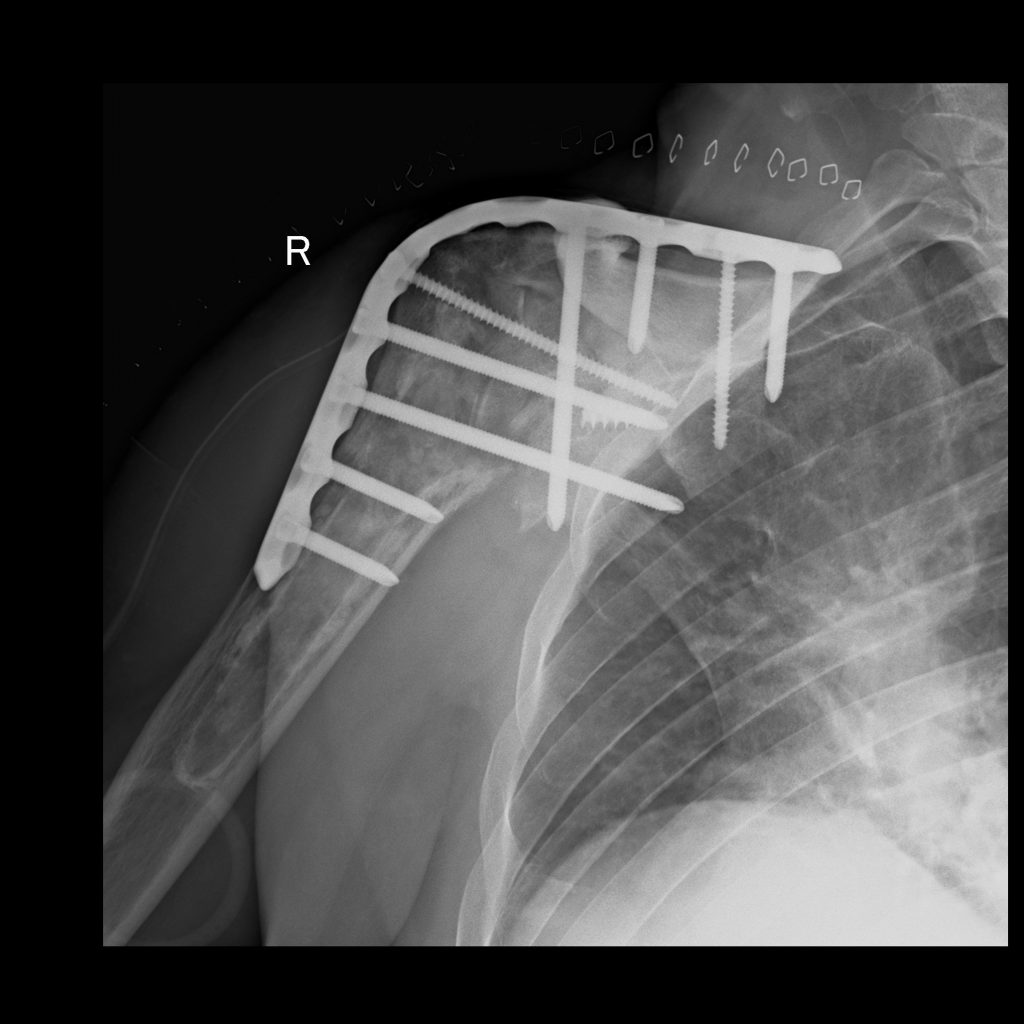

SHOULDER ARTHRODESIS

Operatively stiffening the shoulder is a very rare operation these days. It is done as a last resort to allow a stable foundation for the arm to function from. Though the motion between the upper arm and the shoulder blade is removed, the shoulder blade can still move quite a bit on the chest wall.

The following is a patient with an unstable replacement and an injury to his axillary nerve due to an unfortunate previous surgery. The condition is not amenable to another solution as the front part of the Deltoid muscle is no longer functional. An arthrodesis gives him a stable platform and a painless joint.